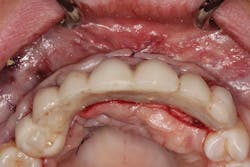

The patient was allowed to heal for three months before returning to uncover the implants. Full thickness flap incisions and retraction of Nos. 5–11 noted bone growth over the implants. We placed polyetheretherketone (PEEK) abutments over the implants to fabricate a fixed screw-retained provisional chairside (figure 9). We grafted once again with PRF, mineralized freeze-dried bone allograft, and fusion bone binder to thicken the area. One horizontal suture was placed from Nos. 7–10. One vertical mattress suture was placed around the No. 5 implant to obtain secondary healing, tucking the PRF membranes over the bone graft on the buccal and lingual tissue and keeping them exposed on the occlusal surface where the temps were screwed in (figure 10) . We allowed this to heal for two months before bringing the patient back to start the restorative phase of treatment (figure 11). During this time, the tissue was able to thicken with the added PRF and additional bone graft added around the implants.

Figure 9: PEEK abutments screwed into implants to convert to fixed temporaries

Figure 10: Temporaries screwed into PRF